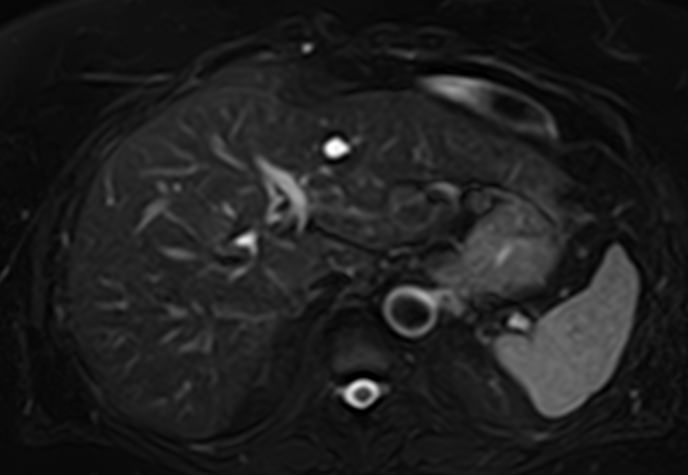

Магнитно-резонансная томография селезенки – высокоинформативный метод исследования органа с использованием внешнего магнитного поля, который позволяет с высокой точностью и достоверностью оценить структуру органа, его размеры, расположение, состояние сосудистой системы и паренхимы селезенки, а также окружающих тканей. МРТ селезенки часто применяется при гематологических заболеваниях, в онкологии, иммунологии.

МРТ селезенки: что показывает

• Новообразования (гемангиомы, саркомы и др.) и метастазы

• Повреждения селезенки (гематомы)

• Сосудистые нарушения (инфаркт, тромбоз вены селезенки, аневризма селезеночной артерии)

• Увеличение селезенки (при портальной гипертензии, болезни Гаучера и т.д.)

• Воспалительные процессы (абсцессы, саркоидоз, гистоплазмоз и др.)

• Кисты селезенки

• Признаки гематологических заболеваний

• Аномалии развития (добавочная селезенка и т.д.)